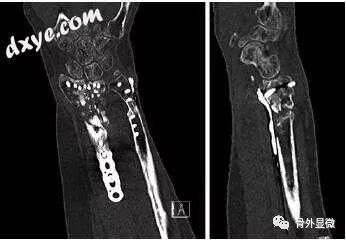

手腕和手的不愈合 骨外显微 微信公众号文章阅读 Wemp